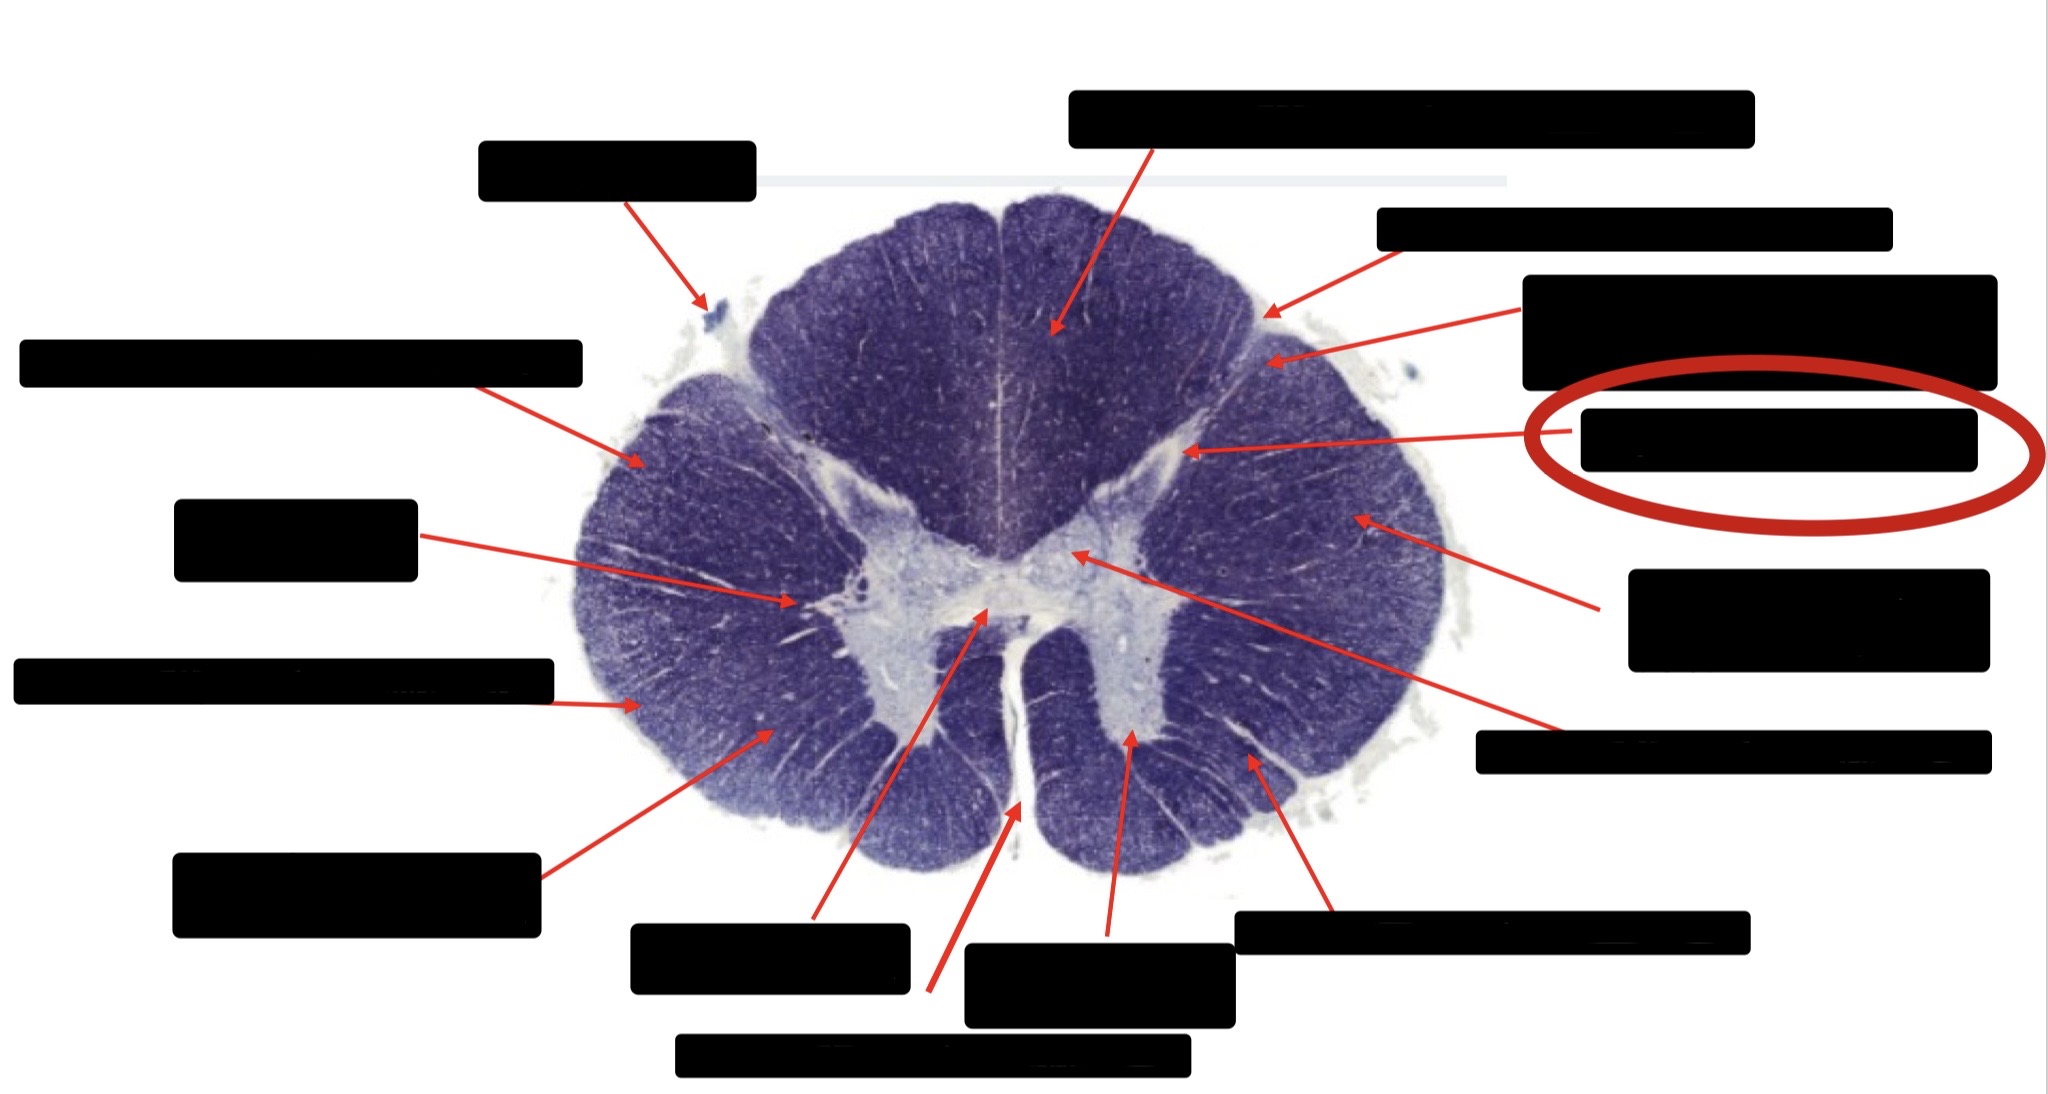

Anterior Spinal Artery

Denticulate Ligament

Ventral Root

Dorsal Root

Posterior Column Fasciculus Gracilis

Large Fiber Entry Zone

Central Canal

Dorsal Rootlet

Lissaeur’s Tract & Small Fiber Entry Zone

Substantia Gelatinosa

Lateral Corticospinal Tract

Anterior Horn Motor Neuron

Spinothalmic Tract

Anterior Horn Motor Neurons